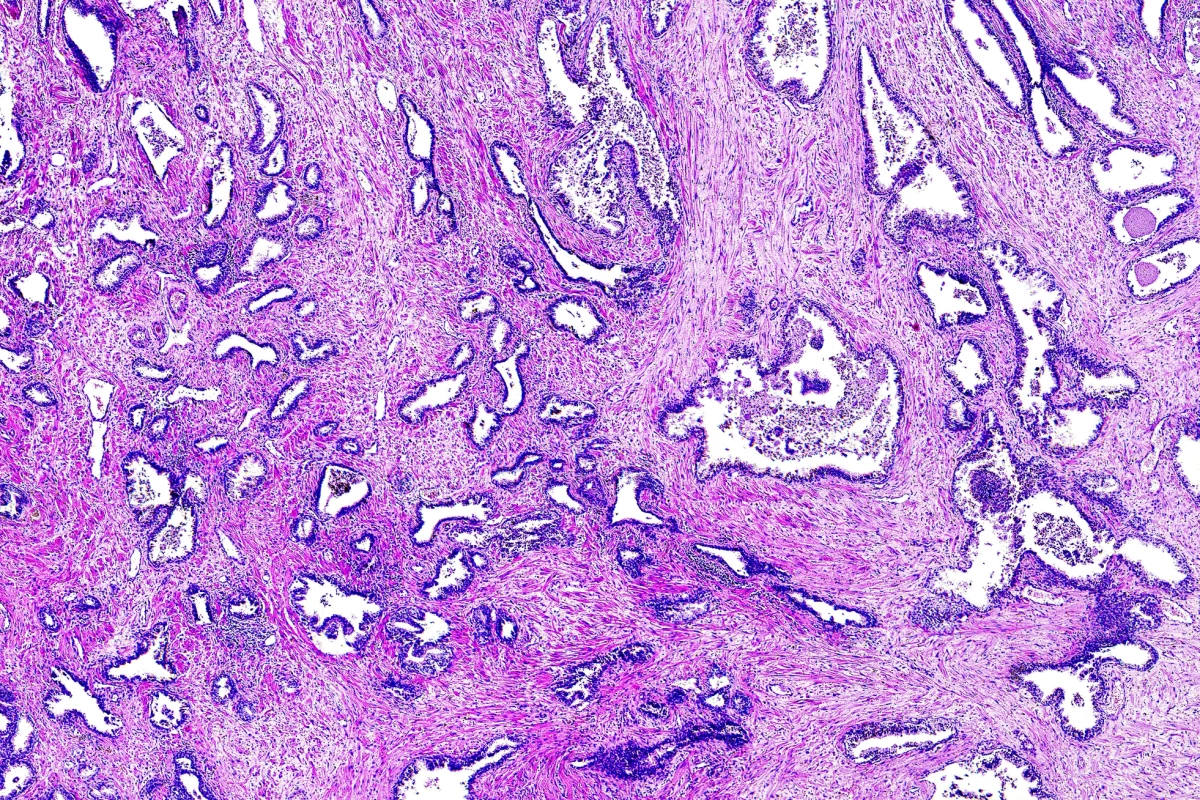

The Gleason score is a mainstay in determining the grade of prostate cancer. A pathologist observes stained cancer cells under a microscope to see how much they look like healthy cells (they get a low score) or abnormal and aggressive cells (high score). This indicates how likely it is that the cancer will advance and spread. A lower-scoring cancer grows more slowly and is less likely to spread than a high-scoring one.

For each patient, the tissue samples were cut into four serial sections. The first section was stained using traditional methods and sent to a board of 11 international genitourinary pathologists, who came to a consensus and assigned a grade to each patient. The remaining sections were labeled with the biomarkers Appl1, Sortilin and Syndecan-1, respectively. Each of the proteins caused different cellular materials to be highlighted. These three tissue sections were then presented to the same 11 pathologists – separated by at least a week to limit the potential for memory bias – and they, on consensus, assigned a grade to each patient.